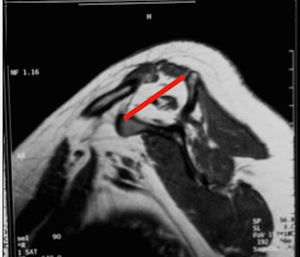

Burkhart desarrolló una clasificación similar basada en la evaluación prequirúrgica con imágenes de RM, en la cual tuvo en cuenta la forma, pero añadía valores numéricos y suprimía la forma trapezoidal, la cual incluyó en las roturas masivas. Todas las roturas se evaluaron en los planos sagital y coronal:

Clasificación de acuerdo con la calidad del tendónLa calidad del tendón se puede evaluar por TC o RM y su función principal es determinar si el tendón, por su calidad, es reparable. La clasificación más usada es la clasificación de Goutallier (tabla 5), basada en la existencia de infiltración grasa en imágenes de TC. Fuchs ha publicado también una clasificación similar con el uso de RM (figs. 3–6).